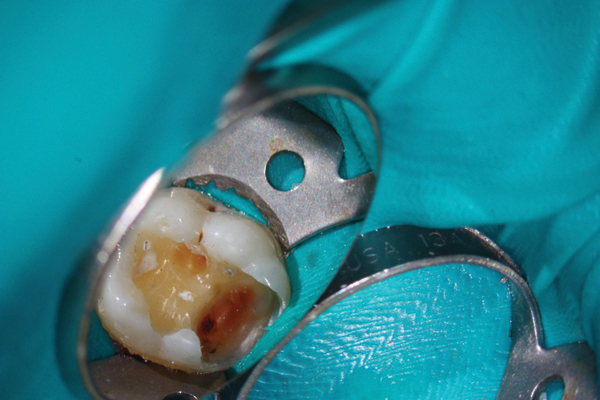

Figure 7. Preoperative pulp exposure after caries removal. Courtesy of Dr. Mohammed A. Alharbi.

Figure 7

Figure 8. Direct pulp coverage with BC Putty. Courtesy of Dr. Mohammed A. Alharbi.

Figure 8